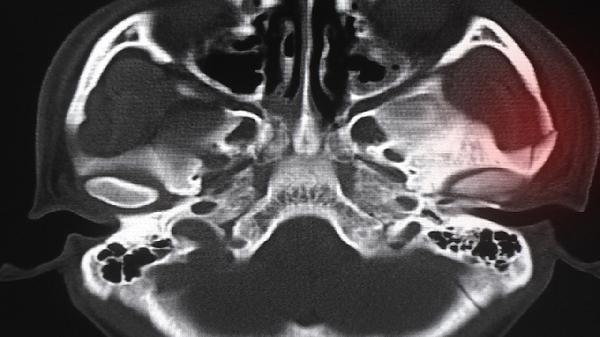

四妙丸由苍术、黄柏、牛膝、薏苡仁组成,具有清热利湿、通络止痛的功效。中医理论认为筋骨疼痛多与湿热下注、经络阻滞有关,该药通过祛除湿热、舒筋活络发挥作用。临床常用于湿热型关节炎、腰椎间盘突出等引起的筋骨酸痛,对伴有下肢沉重、关节红肿热痛的症状可能有一定缓解作用。

但筋骨疼痛病因复杂,若由骨折、肿瘤、风湿性关节炎等非湿热证型引起,或患者存在脾胃虚寒、阴虚火旺等情况,则不宜使用。孕妇及过敏体质者也需禁用。部分患者服药后可能出现胃肠不适,需及时停药就医。